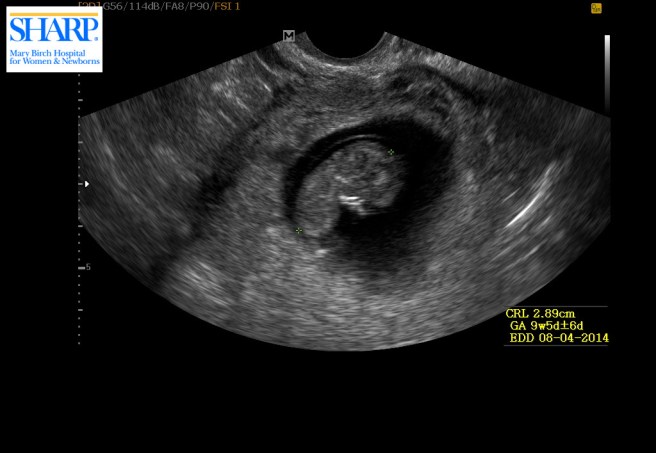

Looks like little Lima Bean is coming along quite nicely 😉 Aren’t we so lucky too to be able to play barefoot in the park in January !!! Good luck on your tests! All will be good :